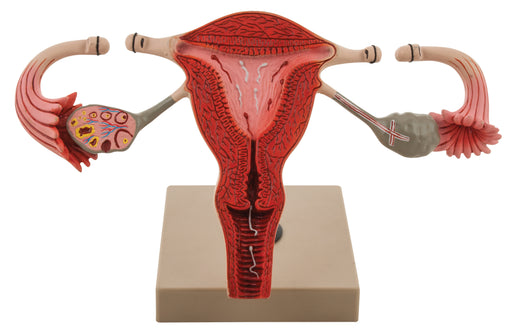

Tubectomy

This 3D model of female tubectomy showing the fallopian tubes are tied off and cut A part. This is done generally for family planning. Size 29 x 15...